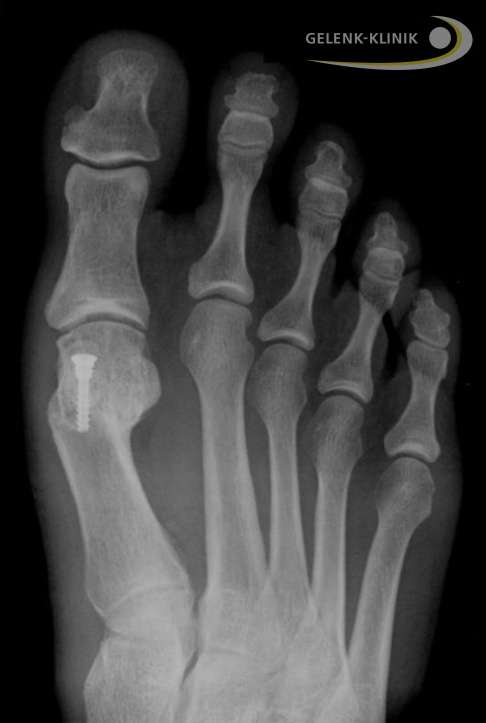

Ergebnis nach minimalinvasiver Hallux valgus-Operation

- Die Operation erzeugt nur minimale Weichteilverletzungen. Die Patienten sind schnell wieder voll belastbar.

- Das Großzehengrundgelenk kann unmittelbar nach der Operation wieder bewegt werden.

- Mit einem speziellen Vorfußentlastungsschuh kann der Patient den Fuß nach der Operation sofort voll belasten.

- Das Fixiermaterial aus der Osteotomie kann meist im Körper verbleiben. Es stellt in der Regel keine Belastung für den Patienten dar. In seltenen Fällen kann das Material ambulant durch einen kleinen Eingriff entfernt werden.

Der Heilungsprozess dauert in der Regel zwischen drei und sechs Wochen. Je schwerer die Fehlstellung war, umso länger dauert die Rehabilitation. Genaue Auskunft über den Zustand des operierten Gelenks gibt eine Röntgenkontrolle etwa vier Wochen nach der Operation.